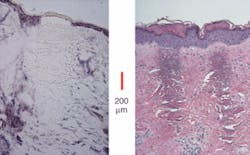

Erbium fiber lasers are also at the heart of the most established commercial fiber laser in the medical arena: the Fraxel SR aesthetic-laser system from Reliant Technologies (Palo Alto, CA). This system, which has U.S. Food and Drug Administration clearance for soft-tissue coagulation, periorbital pigment reduction, sun spots, and skin resurfacing, utilizes a 30-W erbium-fiber laser (from IPG) operating at 1550 nm that works in conjunction with Reliant’s proprietary scanning system to achieve very precise resurfacing and remodeling of the skin while minimizing the collateral thermal damage (see Fig. 4).According to Len DeBenedictis, founder and chief technology officer of Reliant, instead of “bulk treating” the skin, the collimated beam of the single transverse-mode fiber laser enables the scanner to form thousands of very small spots on the treatment surface in a very short period of time. The system is designed to treat about 20% of the skin in a single session; the goal is to treat the face in 20 minutes by creating 1 million “microthermal zones,” each one-tenth of a millimeter across but penetrating hundreds of microns deep into the tissue. The epidermis is then shed and new epidermis created; in addition, the extremely high beam quality of the laser denatures the dermis in a needle-like projection that does not kill the surface tissue. The result, DeBenedictis says, is “nonablative resurfacing.”